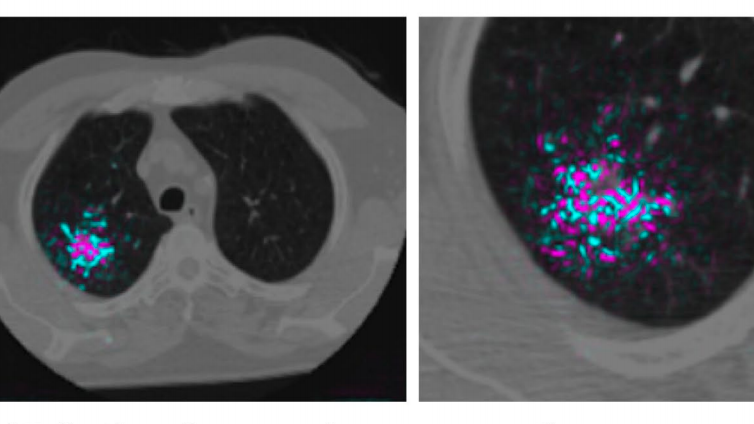

グーグルの研究者であるダニエル・チェが開発したアルゴリズムの検査精度が、多くの熟練の放射線科医の検査精度を上回った。チェと同僚らは4万2000枚以上のコンピューター断層撮影(CT)スキャン画像を使って、悪性肺結節を検出するように深層学習アルゴリズムを訓練した。結果として得られたアルゴリズムは、偽陽性(本来は陰性であるのに誤って陽性と判定されること)の件数が放射線科医に比べ11%少なく、偽陰性(本来は陽性であるのに誤って陰性と判定される)の件数が放射線科医に比べて5%少なかった。研究論文は、5月20日付けのネイチャー誌に掲載されている。